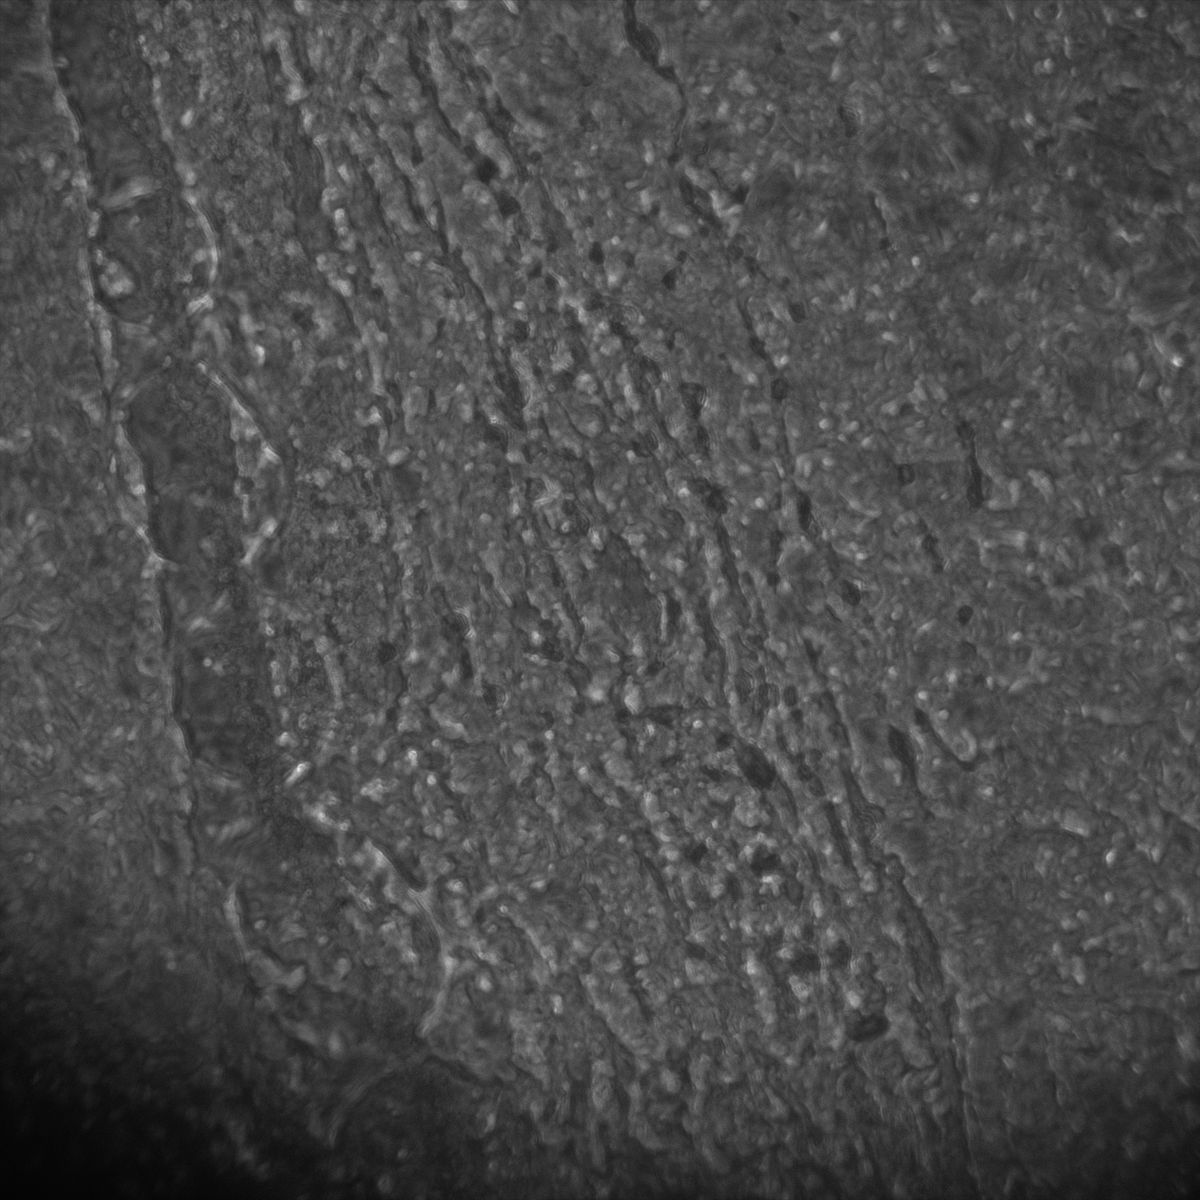

Tubulin

Tubulin - Bip

Tubulin - Nuc